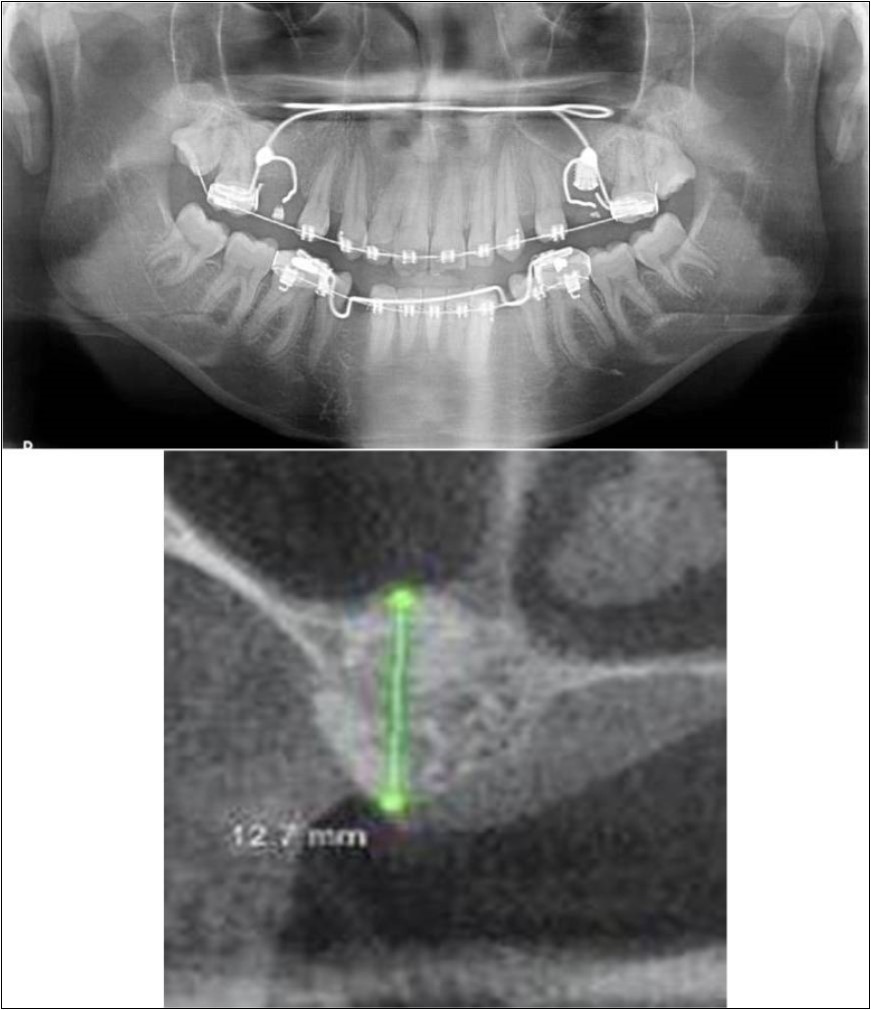

Figure 14.(a,b) Post-treatment OPG and cross section of CBCT showing residual alveolar bone height for Case No.4;

Patient underwent the procedure of indirect sinus elevation using sinus osteotomes in relation to 26 region. Calcium phosphosilicate putty was dispensed as the graft material through the crestal osteotomy site to maintain the elevated sinus membrane followed by placement of 5 x 10mm dental implant under local anaesthesia and strict aseptic protocols. The implant was allowed to osseo-integrate for a period of six months during which the patient was followed-up periodically and was assessed for peri-implantitis, crestal bone loss and mobility. Patient was taken-up for direct sinus elevation via lateral window approach for sinus augmentation i.r.t 16 region. Under aseptic conditions and local anaesthesia, lateral wall of maxilla was exposed after muco-periosteal flap elevation. A window was created of 1cm diameter corresponding to apical aspect of 16. Sinus membrane was identified and elevated using sinus elevators and reamers without perforating the lining. Once the sinus membrane was elevated, phosphosilicate putty was dispensed through the lateral osteotomy site as the graft material to achieve an augmentation of 1cm assessed clinically and confirmed using post-operative OPG. At the end of 6 months, a repeat CBCT scan was advised to evaluate the increase in bone height. (Figure 13a,b, pre-treatment; Figure 14a,b, post-treatment)